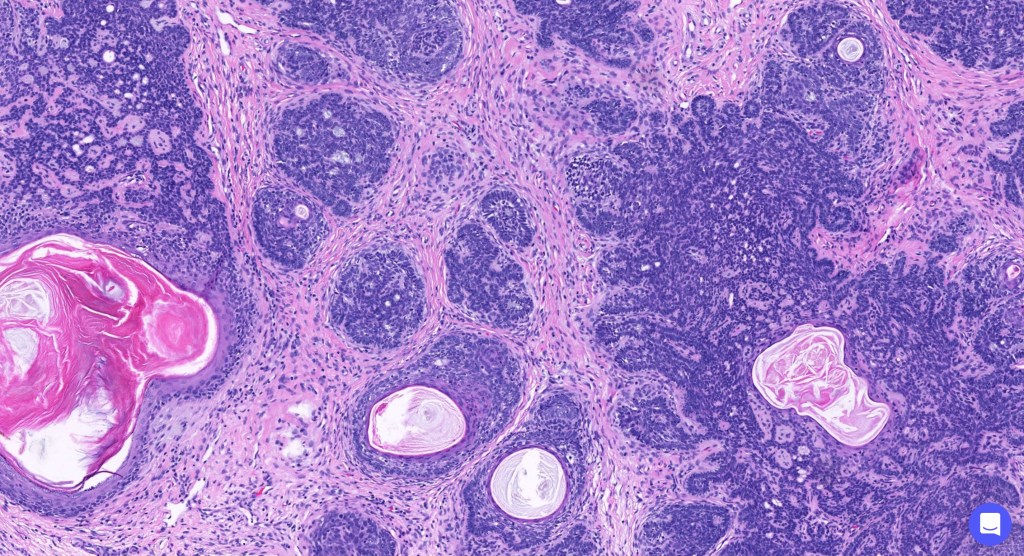

•The classical appearance consists of keratocysts & lobules of basaloid cells

•Basaloid lobules show peripheral palisading

•Perifollicular mesenchyme is always conspicuous and sometimes densely aggregated are seen indenting the baslaloid lobules (papillary mesenchymal bodies)

•Narrow epithelial strands arising from the basaloid lobules are often present

•Amyloid, foreign body granuloma formation to free keratin & calcification are variable features

Trichoepithelioma should be distinguished from trichoblastoma since the latter is very rarely syndromic. Trichoepithelioma is largely a dermal tumor whereas trichoblastoma often extends from the dermis into subcutaneous fat or deeper in very large examples. Papillary mesenchymal bodies are much better formed and generally more obvious in trichoepithelioma. Trichoepithelioma must also be distinguished from basal cell carcinoma. Retraction artifact & stromal mucin are features of basal cell carcinoma and not trichoepithelioma. Papillary mesenchymal bodies are not seen in basal cell carcinoma.